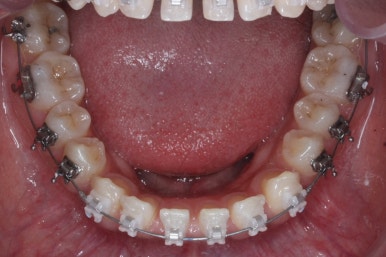

장치 부착 모습입니다.

이번에 부산치아교정치과에서 사용한 장치는 클리피씨라는 자가결찰 세라믹입니다.

다음 단계는 작은 어금니 부위에 모아진 틈을 없애는 것입니다. 앞서도 말씀을 드렸듯이 앞니의 앞-두로의 위치는 변화 시키면 안되기 때문에 오로지 어금니를 앞으로 당겨오면서 틈을 모아줘야 합니다.

어금니를 100% 당겨주는 방법은?

바로 미니스크류 입니다. 위 사진에서 화살표 부분이 바로 미니스크류 입니다.

뼈에 단단히 고정해 놓고 어금니를 앞으로 당겨오는데 사용을 하게 됩니다. 교정치료 후에는 제거하게 되며 긍방 뼈가 차기 때문에 별로 걱정은 하지 않으셔도 됩니다.